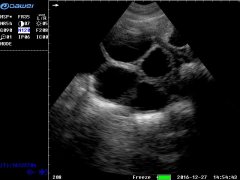

B超機

大為超聲專業生產

的廠家,包括:

醫用B超機

,

黑白B超機

彩超機

獸用B超機